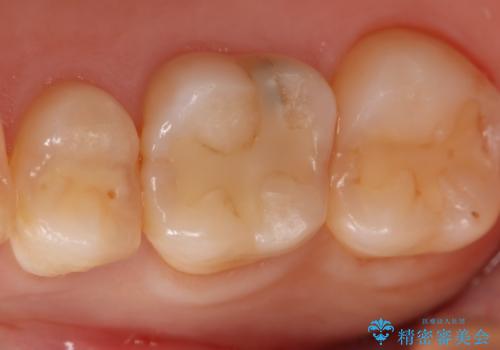

- 右上6番の虫歯治療を主訴に来院された患者様です。

切削量・形態を考慮し、セラミックインレーでの治療を計画しました。

保険の材料が劣化し中で虫歯が進行していたので、全て取り除いた上で形を整え型をとりインレーをセットしています。